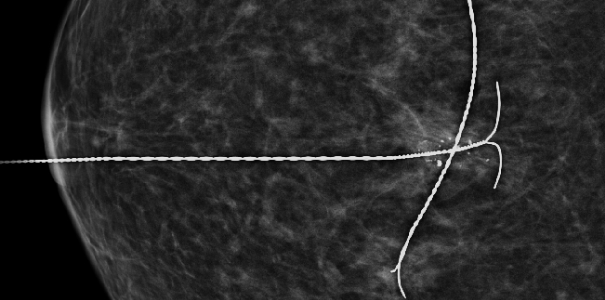

이런 경우 예전에는 갈고리형의 침을 꽂아 유방에 넓은 부위를 절개하여 조직검사를 진행했으나

본 원에서는 진공흡인 보조장치(맘모톰)를 통해 특수한 바늘로 병변 위치, 크기 등을 세밀히 확인할 수 있고(침 위치 결정 술)

해당 병변 조직을 채취하여(조직검사) 빠른 시일 내 암 또는 양성 결절(혹, 종양)을 진단 할 수 있게 되었습니다.

과거 여러 번 유방촬영을 진행하였지만 진단하기 어려운 치밀유방으로 인해 정상 판정을 받다가

진공흡인 보조장치(맘모톰)의 특수바늘을 통해 병변 확인해 보니

우측 유방 윗부분에 미세 석회가 발견되어조직 채취 후 암 진단 판정되어 치료 진행

치밀유방 여성, 우측 미세석회 발견